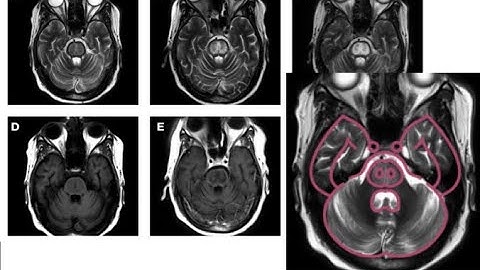

Movement Disorder After Too-Rapid Correction of Hyponatremia And Osmotic Demyelination Syndrome